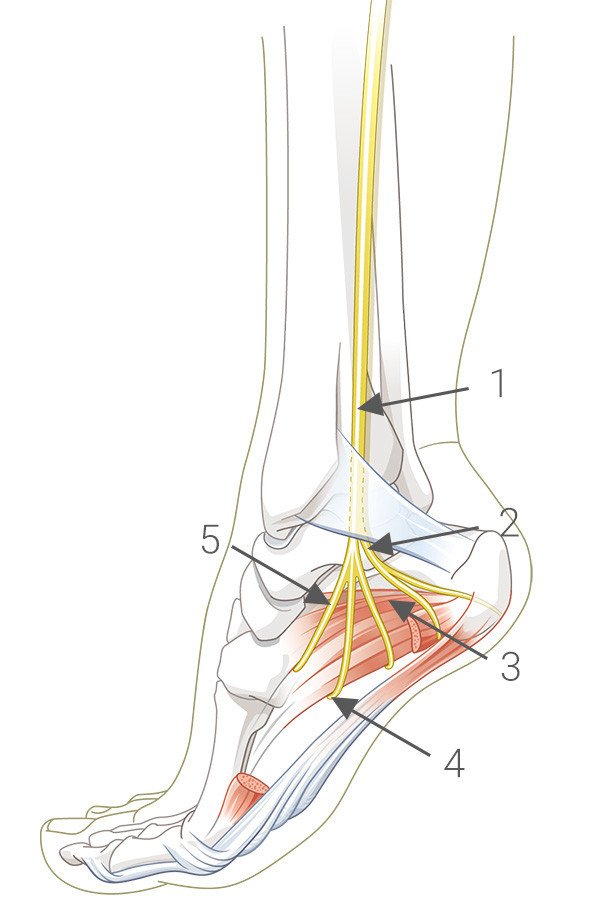

Die Untersuchung in unserer Sprechstunde zeigte an der „klassischen“ Stelle des Fersensporns keine Druckschmerzen. Hingegen fand sich jedoch im Verlauf eines kleinen Nervs, der an der Innenseite des Fersenbeins entlang läuft eine deutlich auszulösende Druckschmerzhaftigkeit. Die Patientin bezeichnete dies als den bekannten Schmerz. Dieser Nerv wird auch als „Baxter Nerv“ bezeichnet.

Wir führten am Tag der Erstkonsultation eine Infiltration des Nervs beidseits durch. Diese wird mit einem Gemisch aus Cortison und einem lokalen Betäubungsmittel ausgeführt.

Hilft die durchgeführte Infiltration des Nervs nur kurzfristig, kann im Verlauf auch eine Operation durchgeführt werden. Der Nerv läuft durch eine Art Tunnel und kann in diesem Bereich eingeengt sein. Durch eine Spaltung des Tunnels kann die Funktion des Nervs wiederhergestellt werden und die Schmerzen lassen nach.